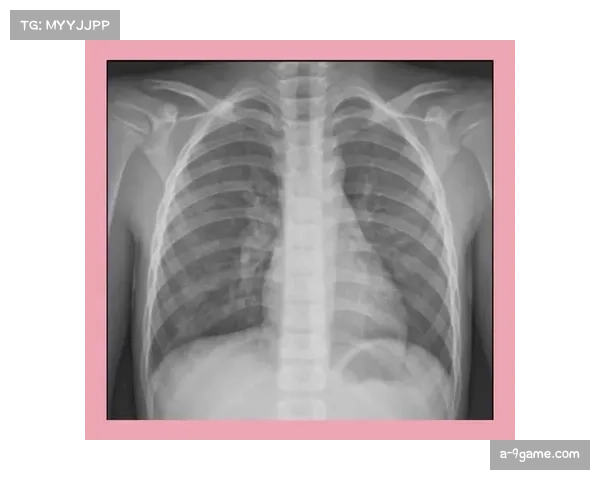

X光检查是医学中用于检测骨折、错位或骨质损伤的一项常规检查方法。对于像雷迪克这样的职业运动员而言,X光检查几乎是每次受伤后必须进行的步骤。雷迪克在受伤后的第一时间就接受了X光检查,结果显示其手腕并没有出现骨折或明显的结构性异常,这对于他的恢复无疑是一个积极的信号。

X光检查主要通过射线透过身体,检测骨骼的密度和结构。通过这种方式,医生可以很清楚地判断出是否存在骨折、关节脱位或者其他由撞击造成的骨骼损伤。在雷迪克的案例中,X光未发现异常,意味着其手腕的骨骼在结构上没有受到严重影响。这为雷迪克提供了一个积极的康复前景,使得他可以尽早进行针对性的康复治疗,避免伤情的恶化。

然而,值得注意的是,X光检查并不能全面显示所有类型的伤害,例如软组织的损伤或肌肉拉伤等。如果雷迪克的手腕出现了肌肉或韧带的损伤,这可能无法通过X光检查得到确认。因此,X光检查虽然排除了骨折的可能性,但并不能完全排除其他类型的伤害。后续的CT扫描或者MRI检查可能会提供更为详细的诊断。